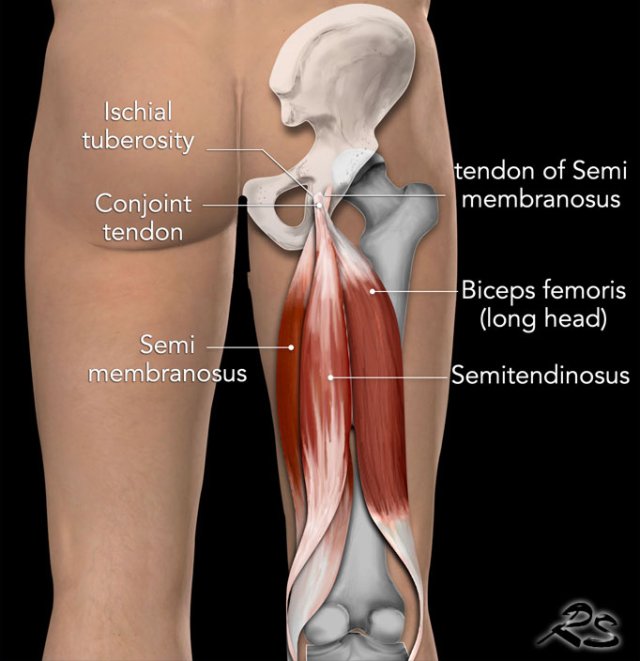

The hamstrings are the muscles in the posterior compartment of the thigh and consist of the biceps femoris, semitendinosus and semimembranosus.

They are innervated by the sciatic nerve and contraction results in extention of the hip and flexion of the knee.

The conjoint tendon is formed by the long head of the biceps femoris laterally and the semitendinosus tendon medially.

The biceps femoris muscle has two heads.

The long head originates from the ischial tuberosity, while the short head originates from the linea aspera on the posterior surface of the femur.

The common tendon of the two heads can be felt laterally at the posterior knee and inserts onto the head of the fibula.

Semitendinosus

The semitendinosus is a largely tendinous muscle, which is located medially to the biceps femoris, and covers the majority of the semimembranosus muscle.

Semimembranosus

The semimembranosus muscle is flattened and broad. It is located underneath the semitendinosus.

The hamstrings insert on the upper region of the ischial tuberosity.

On this posterior view you will notice that the semimembranous tendon inserts on the lateral side, while the muscle is located medially.

The Conjoint tendon of the biceps femoris and the semitendinosus inserts on the medial facet.